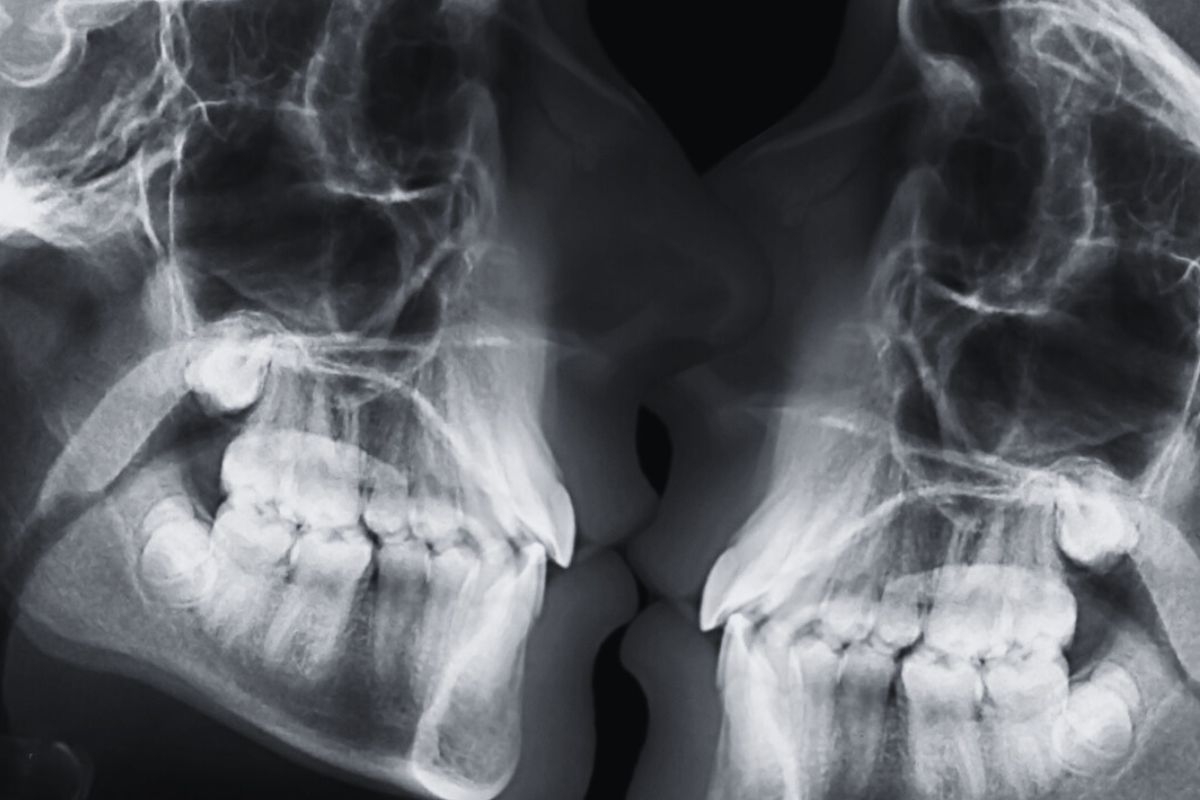

Το αρχείο εικόνων απέδειξε κάτι που μέχρι τότε αγνοούσε η ιατρική κοινότητα. Ο κολπικός σωλήνας δεν είναι ευθύς, αλλά καμπυλωτός. Παράλληλα, οι εικόνες έδειξαν πως το αντρικό πέος προσαρμόζεται και κάμπτεται ώστε να ταιριάζει στο σχήμα του γυναικείου σώματος.

Αυτά τα ευρήματα ήρθαν σε πλήρη αντίθεση με απεικονίσεις από τις μέρες του Λεονάρντο ντα Βίντσι, στις οποίες ο κόλπος παρουσιάζεται ως ευθύς κυλινδρικός σωλήνας, σε μια λανθασμένη αντίληψη που είχε επικρατήσει για περισσότερα από 500 χρόνια..